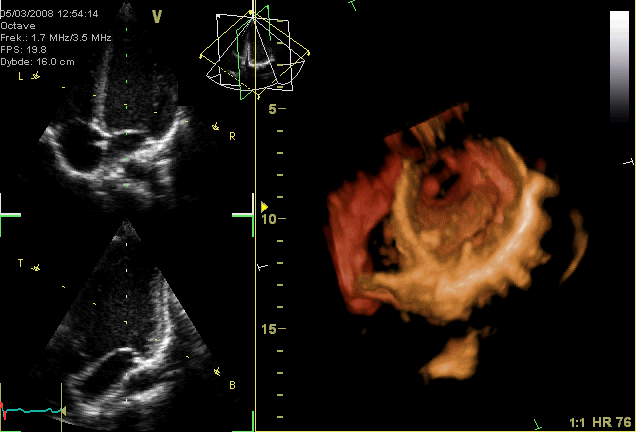

• 13-13:45 エコー講義

• 14:10- エコーデモ前説

• 14:20-15 エコーデモ 被験者1で配信、続いて数名検査されたりしてみたり